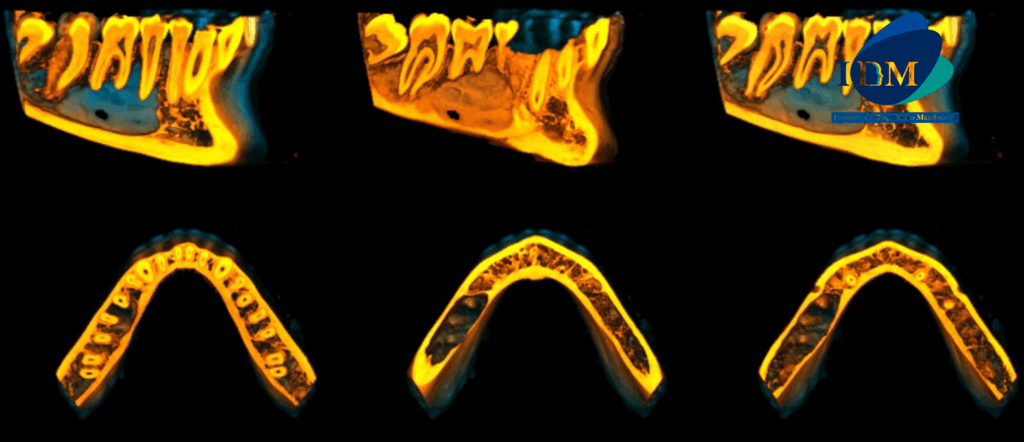

En las reconstrucciones 3D se representa de manera didáctica Quiste Óseo Simple (Figura 4).

RECONSTRUCCIÓN 3D